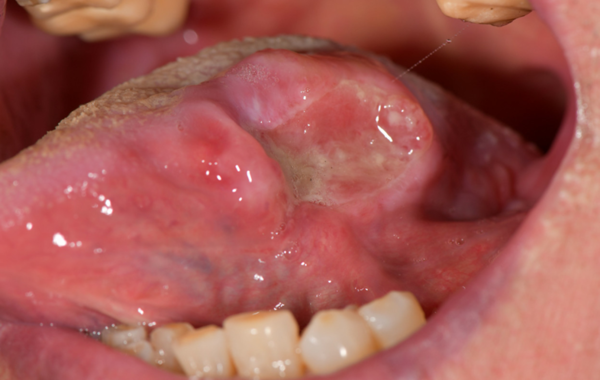

구강질환은 고양이에게 흔하며, 고양이 역시 개보다 구강질환에 걸리기 쉽고, 구강 내부를 관찰하기 어려워 증상을 의심하기 어려워 질병 진단이 늦어진다. 구내염은 구강 전체의 구강 점막 염증입니다. 잇몸, 혀, 목에도 발생할 수 있습니다.

구내염의 정확한 원인은 없으나 단일 원인보다는 치석, 세균, 면역계 이상 등이 복합적으로 작용하여 발생하는 것으로 생각됩니다.

고양이 구내염은 제때 치료하지 않으면 다른 구내염과 달리 인후염이 동반되어 음식을 씹을 때 뿐만 아니라 삼킬 때 통증까지 생겨 아이들이 밥을 잘 못 먹게 됩니다.